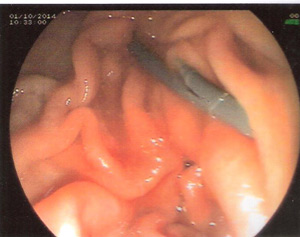

ERCP was performed.Selectuve cannulation was done of the pancreatic duct .The wire could negotiate the stricture in the neck but even a 5 Fr biliary dilator could not.A stent retriever was screwed over the wire and the stricture dilatation obtained with removal of fragments of stone.A pancreatic stent was placed .

The stent was removed after 2 months to obtain free pancreatic duct drainage.The patient was pain free.